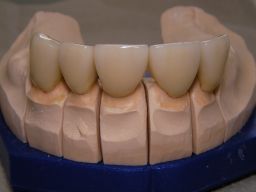

Die Bilder können alle angeklickt werden! Das Hauptproblem dieses Falles lag im Oberkiefer - die über die Jahrzehnte abgeknirschten, kurzen Zähne erschweren Kronen, die durch eine Prothese belastet werden können. Die gewählte Lösung besteht darin, die Zähne nur rundherum zu beschleifen, aber nicht mehr zu kürzen und die Prothese mit einem Druckknopfsystem an die Zähne anzukoppeln, das ein "Spiel" aufweist, so daß die Prothese nicht als Hebelarm auf die schwachen Restzähne wirken kann. Rechts die beschliffenen Zähne kurz vorm Zementieren der Kronen. |

Links das Bild zeigt das Metallgerüst, das später mit Keramik verblendet wurde. Um eine einfache Mundhygiene ebenso wie eine hohe zahntechnische Präzsion zu erreichen, wurden risikobehaftete Verblockungen minimiert. Rechts die Ästhetikeinprobe bei entspannter Oberlippe. |

Links Bilder des Oberkiefers, rechts des Unterkiefers. Die Arbeit wurde von dem Dentallabor "Heitmeyer Zahntechnik", Osnabrück, gefertigt. Dem Labor ist hier für die hervorragende Arbeit zu danken, dem Patienten für die Freigabe der Bilder! |